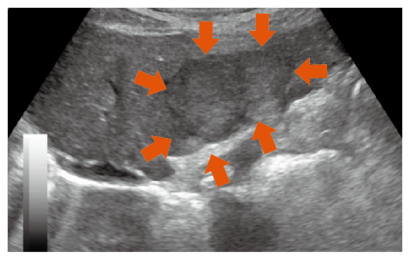

肝臓に腫瘍があるかどうかは、画像診断でわかります。もちろん良性の場合もありますが、肝機能が落ちてから画像を撮ってみたら大きい腫瘍が見つかった…というケースも。

脂肪肝から肝がんへのリスクが高い糖尿病の患者さんや予備軍に当たる人は、年に一度を目安に、かかりつけ医でお腹のエコーを撮ることをお勧めします。

二次検査で腫瘍が見つかった場合は、造影CT検査や造影MRI検査を行い、それでも診断がつかない場合は、超音波ガイド下肝生検で組織を採るなどしてさらに詳しく調べていきます。当院では高性能の超音波診断装置を数台そろえ、超音波造影剤を用いた検査は全国トップレベル、副作用もほとんどありません。